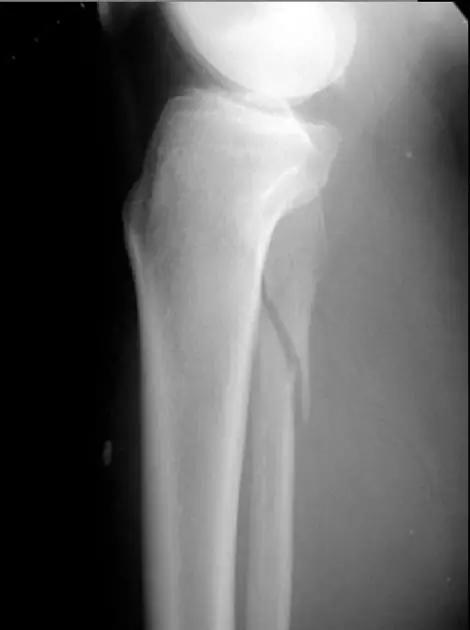

11. Bumper 骨折 (保险杆骨折)

是汽车保险杠撞击膝关节外侧,导致的胫骨平台粉碎性骨折,伴有软骨面挫裂和腓骨头骨折。初诊,X 线上正侧位很容易轻忽平台的粉碎性,CT 平扫及重建可明确伤情,MRI 可了解副韧带及叉韧带情况。